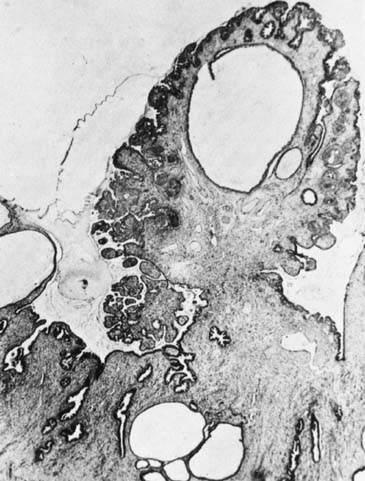

Papillomas that are not HPV-related can occur in the cervix and usually originate from the exocervix near the squamocolumnar junction (transformation zone). These are thought to be related to local irritation or scarring and are usually less than 1 cm. Their natural history is not well described, as the usual intervention for these papillomas is excision to assure that this does not represent malignancy1 (Figs. 5 and 6).

Fig. 5. Squamous papilloma of the cervix.

Fig. 6. Benign squamous papilloma of the cervix.